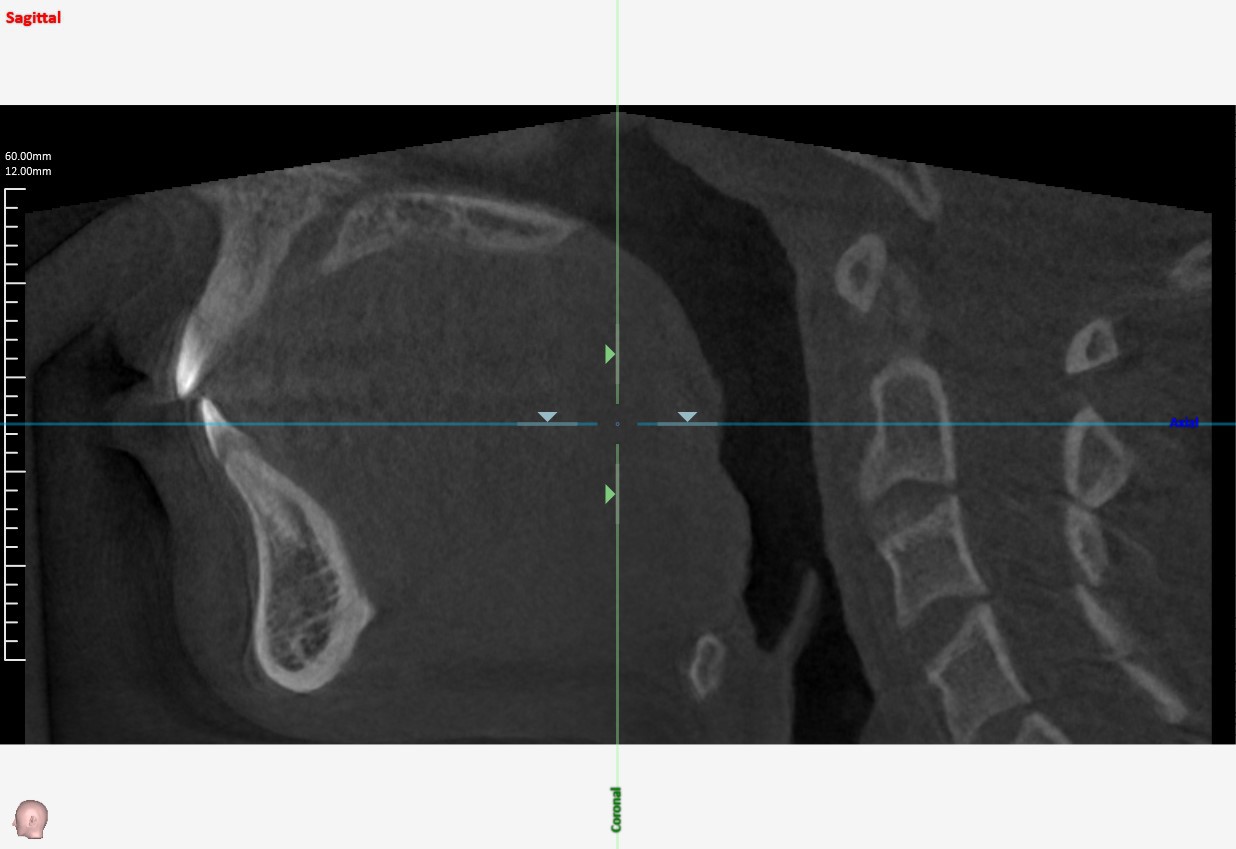

咽頭CT

3D画像撮影なども可能です。

※ただし軟部組織の撮影は苦手なので頸部のCTは総合病院に依頼します